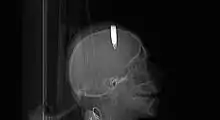

Les munitions non explosées posent des problèmes médicaux spécifiques :

- en cas de patient blessé par une balle explosive ou munition de taille plus importante non explosée encore présente dans le corps. Outre les risques chirurgicaux classiques, le risque d'explosion doit être pris en compte par le chirurgien (le bistouri électrique devrait par exemple être utilisé avec précaution) ;